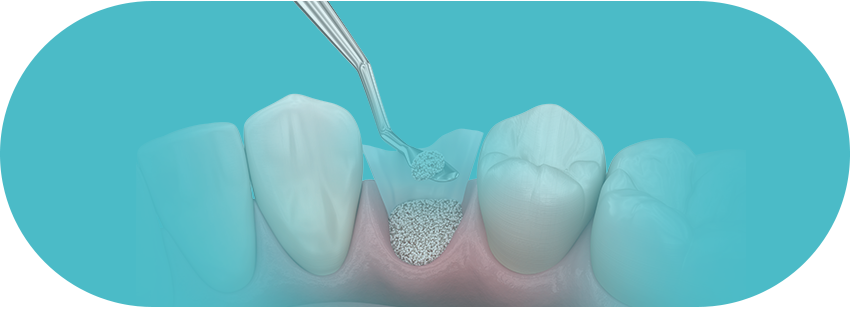

뼈이식 임플란트

고난도 뼈이식술은 치과의사의

경험이 매우 중요합니다.

걱정하지 마세요!

풍부한 임상경험과 노하우로

뼈가 부족한 경우, 고혈압, 당뇨, 전신질환이 있어도

자신있습니다!